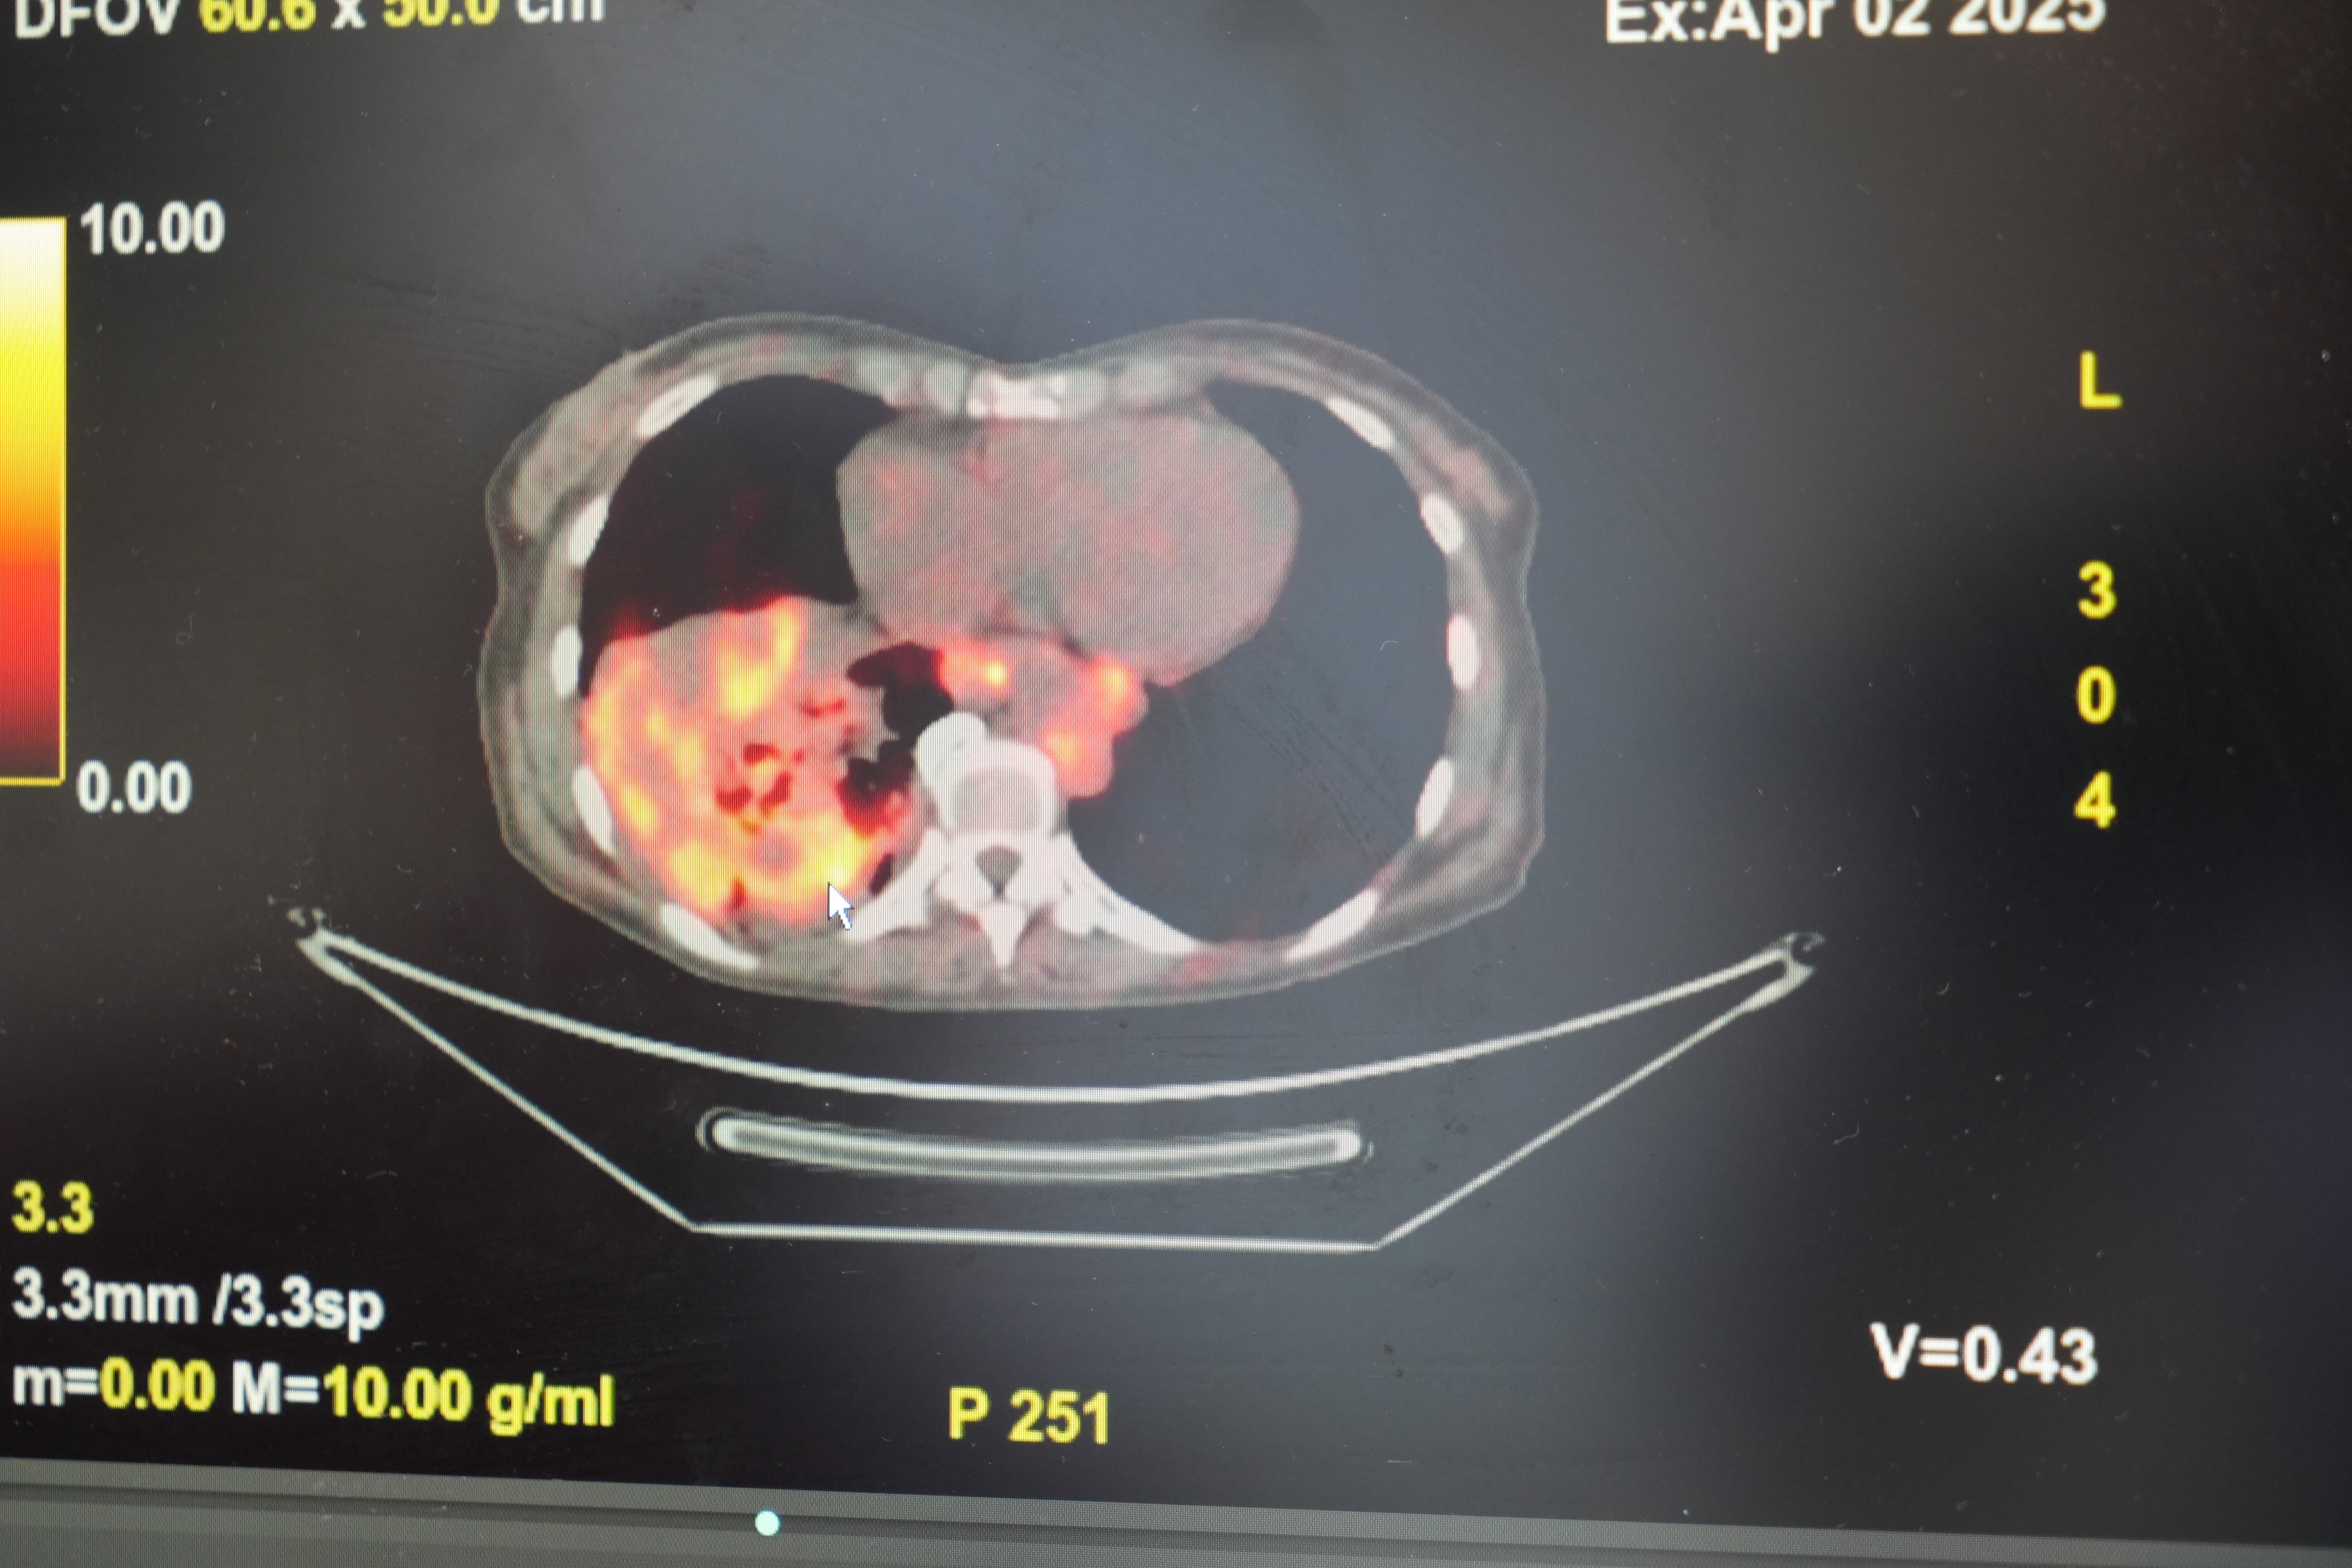

'Sigarasız akciğer kanseri' vakalarında dikkat çeken artış!

Göğüs Hastalıkları Uzmanı Prof. Dr. Şevket Özkaya, son yıllarda sigara kullanmayan bireylerde de akciğer kanseri vakalarının dikkat çeken bir oranda arttığını belirterek, özellikle kadınlarda görülen adenokarsinom tipi akciğer kanserinin artış gösterdiğine dikkat çekti. Bu konuda yapılan son araştırmalara değinen Özkaya, akciğer kanseri teşhislerinin yaklaşık yüzde 20’sinin hiç sigara içmemiş bireylerde konduğunu söyledi.